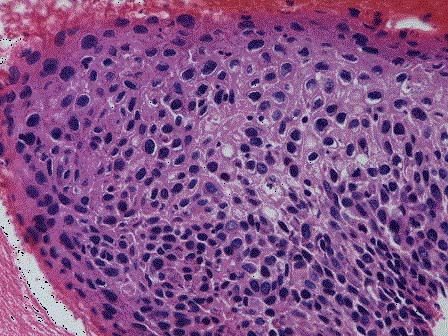

问题 女性,39岁,接触性出血,曾查有CINⅡ级。经治疗后复查,取宫颈组织活检,镜下见鳞状上皮排列不规则,细胞异型性明显,累及上皮全层(如图)。应诊断为 ( )

选项 A.宫颈CINⅠ级 B.宫颈CINⅡ级 C.宫颈CINⅢ级 D.宫颈原位癌 E.宫颈浸润性癌

答案 D